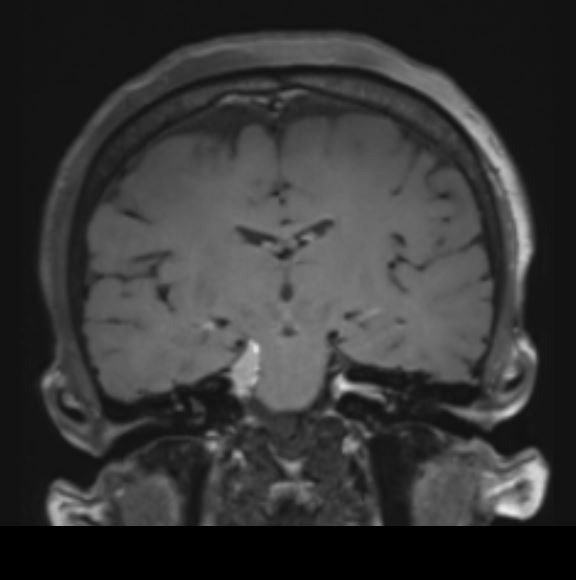

Ευμεγέθες Ενδοκοιλιακό Μηνιγγίωμα Δεξιά

Ασθενής γυναίκα, 70 ετών παρουσίασε επιληπτικές κρίσεις και αριστερή ημιανοψία. Η μαγνητική τομογραφία ανέδειξε ευμεγέθη χωροκατακτητική εξεργασία εντός της δεξιάς πλάγιας κοιλίας του εγκεφάλου. Διενεργήθη

Ενδοκοιλιακό Μηνιγγίωμα Δεξιά

Ασθενής γυναίκα, 59 ετών παρουσίασε επεισόδιο επιληπτικής κρίσης. Η μαγνητική τομογραφία ανέδειξε ευμεγέθη χωροκατακτητική εξεργασία εντός της δεξιάς πλάγιας κοιλίας του εγκεφάλου. Διενεργήθη διαφλοιική προσπέλαση